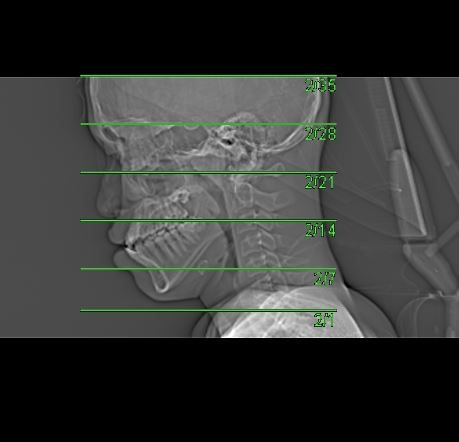

Topogram

• Position the patient in head first supine position.

• Align the patient in Mid-Sagittal plane of the table.

• Position the transverse laser light beam at the level of 1 inch above head vertex.

Topogram Parameters

• Topogram length: 256 cm

• Slice: 0.6 mm

• Scanning direction: Craniocoudal

• Tube position: Lateral

• Stop the topogram scanning when the scanning reach / pass over the chin

Non Contrast

• Plan the Scan FOV (SFOV) box at topogram image

• Set the top line at the level of head vertex.

• Set the bottom line at the level of mental protuberance.

• Ensure the lateral line to cover patient’s facial superficial structure (nasal bone) and skull.